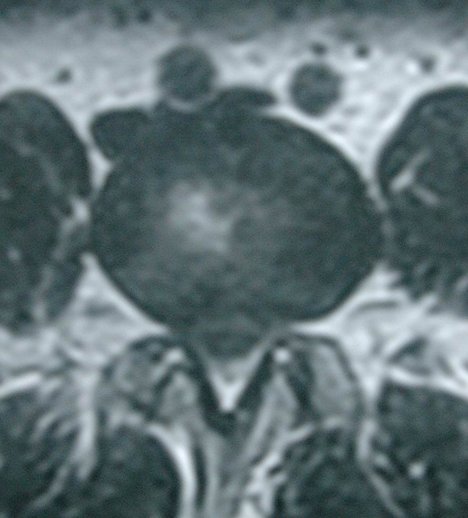

둘째, 허리디스크의 예후는 척추관(vertebral canal) 크기와 디스크 탈출 정도(Barrel and Contents mechanism)와 관련이 있습니다. 즉 척추관(vertebral canal) 형태가 작고, 아래 그림과 같이 클로버잎(trefoil shape) 형태인 경우에는 디스크가 약간만 탈출돼도 신경근(nerve root)이 심하게 압박되어 심한 통증과 근위약, 근위축 등 심각한 증상이 나타날 수 있습니다.

이것은 컴퓨터단층촬영(CT), 자기공명영상(MRI) 축(axial)사진으로 쉽게 확인할 수 있습니다. 반대로 척추관이 넓으면 디스크 탈출이 심해도 신경근(nerve root) 압박은 미미하여 통증이 가볍고 신경학적 증상도 가벼울 수 있습니다. 특히 급성 허리디스크 환자에서는 척추관 크기와 디스크 탈출 정도에 따른 예후 판단과 신경학적 검진에 의한 예후판단이 매우 중요합니다.

그림. trefoil shape 척추관과 디스크 탈출 사진

그림. 넓은 척추관과 디스크 탈출사진